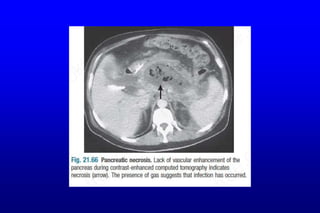

 CE CT, 6–10 days after admission useful in assessing viability, if persisting

organ failure, sepsis or clinical deterioration; features of pan necrosis.

 Necrotising pancreatitis is associated with decreased pancreatic

enhancement on CT, following IV contrast inj.

 The presence of gas within necrotic material suggests infection&impending

abscess formation, in which case percutaneous aspiration of material for

bacterial culture, for appropriate antibiotics.

Acute pancreatitis :imagings  U/S can confirm the diagnosis, although in the earlier stages the gland may not be grossly swollen,also useful because it may show gallstones, biliary obstruction or pseudocyst formation.  CE CT, 6–10 days after admission useful in assessing viability, if persisting organ failure, sepsis or clinical deterioration; features of pan necrosis.  Necrotising pancreatitis is associated with decreased pancreatic enhancement on CT, following IV contrast inj.  The presence of gas within necrotic material suggests infection&impending abscess formation, in which case percutaneous aspiration of material for bacterial culture, for appropriate antibiotics.  Involvement of the colon, blood vessels&other adjacent structures by the inflammatory process is best seen by CT.